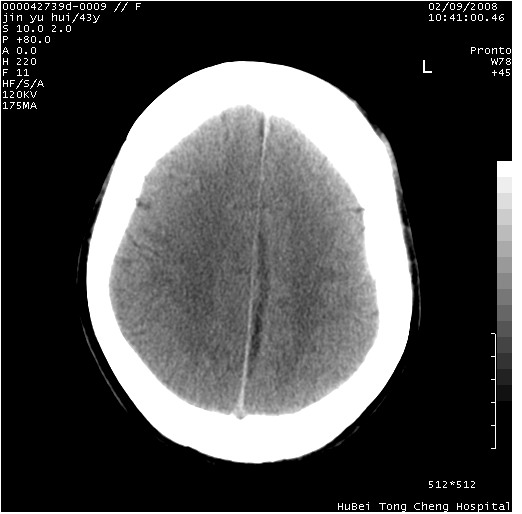

患者 女,43岁。头部外伤26天,经住院治疗,现头痛减轻。申请ct复查,了解颅内情况。

临床诊断:2级脑外伤。

颅脑ct轴位平扫(层厚、层距均为10mm),图像如下:

伴硬膜下水瘤

纵裂旁硬膜下水瘤,左额部头皮肿胀

大脑镰左旁硬膜下血肿慢性期。

大脑镰左旁慢性硬膜下血肿.

大脑镰左旁慢性硬膜下血肿.左额部头皮血肿.

是不是应该为:大脑镰左旁硬膜下血肿吸收期更妥当些;